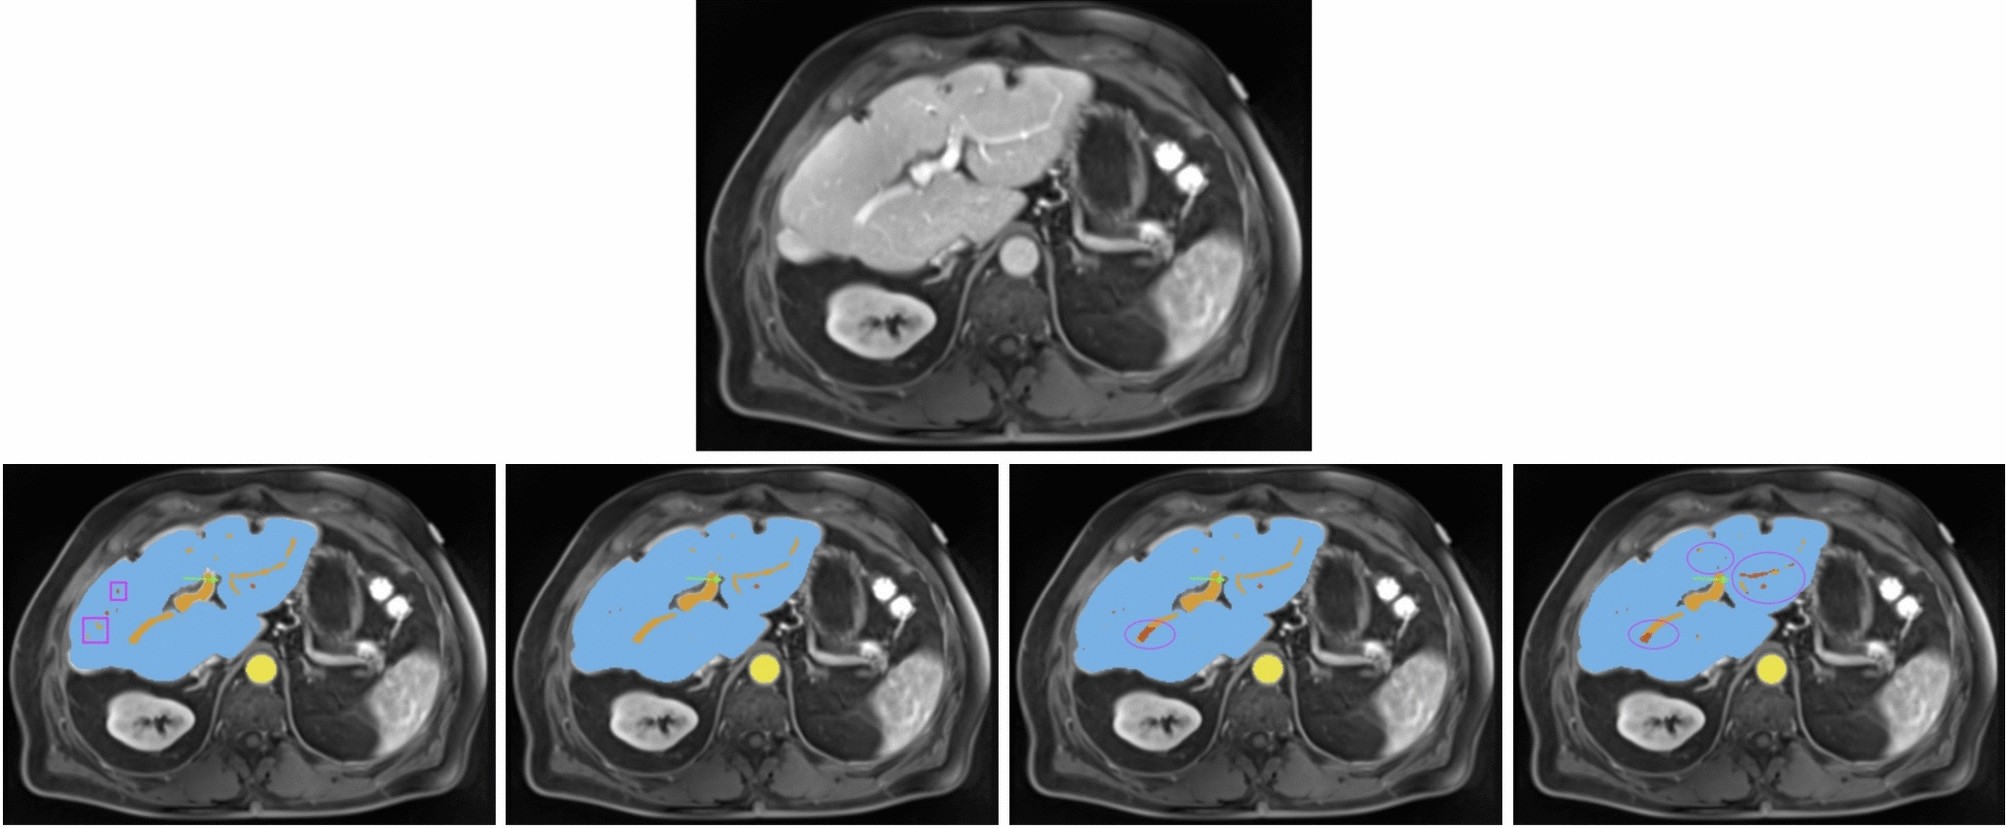

Fig. 3

All images show the same axial section of a patient with liver disease for the portalvenous phase. First row is the given image with no annotations. Labels in the other images are blue (liver), orange (portal vein), red (hepatic vein) and yellow (abdominal aorta). The bottom row from left to right depicts the ground-truth annotations, standard nnU-Net’s, ResEnc nnU-Net’s and SWIN UNETR’s segmentations. Arrows and ellipses highlight major differences between the segmentations from the models and the ground-truth annotations. The pink rectangular boxes show hepatic and portal veins in the ground-truth annotations that all of the architectures missed.